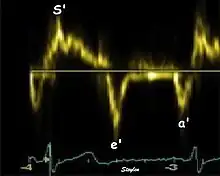

Diastolic function

As the ventricle relaxes, the annulus moves towards the base of the heart, signifying the volume expansion of the ventricle. The peak mitral annular velocity during early filling, e' is a measure of left ventricular diastolic function, and has been shown to be relatively independent of left ventricular filling pressure.[12][13][14] If there is impaired relaxation (Diastolic dysfunction), the e' velocity decreases. After the early relaxation, the ventricular myocardium is passive, the late velocity peak a' is a function of atrial contraction. The ratio between e' and a' is also a measure of diastolic function, in addition to the absolute values.

During the two filling phases, there is early (E) and late (A) blood flow from the atrium to the ventricle, corresponding to the annular velocity phases. The flow, is driven by the pressure difference between atrium and ventricle, this pressure difference is both a function of the pressure drop during early relaxation and the initial atrial pressure. In light diastolic dysfunction, the peak early mitral flow velocity E is reduced in proportion to the e', but if relaxation is so reduced that it causes increase in atrial pressure, E will increase again, while e', being less load dependent, remains low. Thus, the ratio E/e' is related to the atrial pressure, and can show increased filling pressure[15][16] although with several reservations.[17][18] In the right ventricle this is not an important principle, as the right atrial pressure is the same as central venous pressure which can easily be assessed from venous congestion.[19][20]